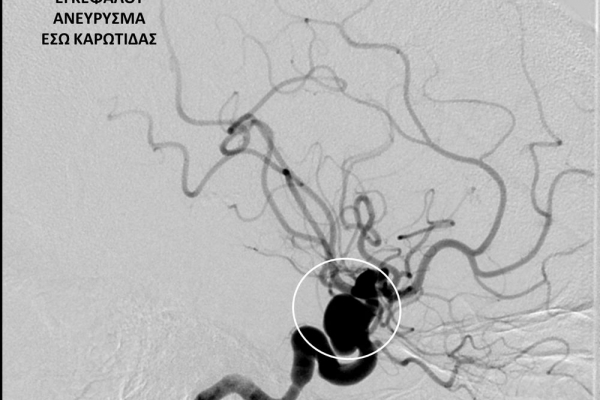

- Η ψηφιακή αγγειογραφία (DSA) αποτελεί την καλύτερη μέθοδο διάγνωσης των αγγειακών παθήσεων.Η αγγειογραφία γίνεται ως εξής: αρχικά παρακεντάται μια αρτηρία πρόσβασης, όπως η μηριαία αρτηρία στη βουβωνική περιοχή ή η βραχιόνια αρτηρία στο βραχίονα. Στη συνέχια προωθείται ένας καθετήρας προς την περιοχή του ενδιαφέροντος και γίνεται η έγχυση σκιαγραφικής ουσίας (σκιαγραφικού) με συνεχή λήψη «εικόνων» των αγγείων-στόχων.